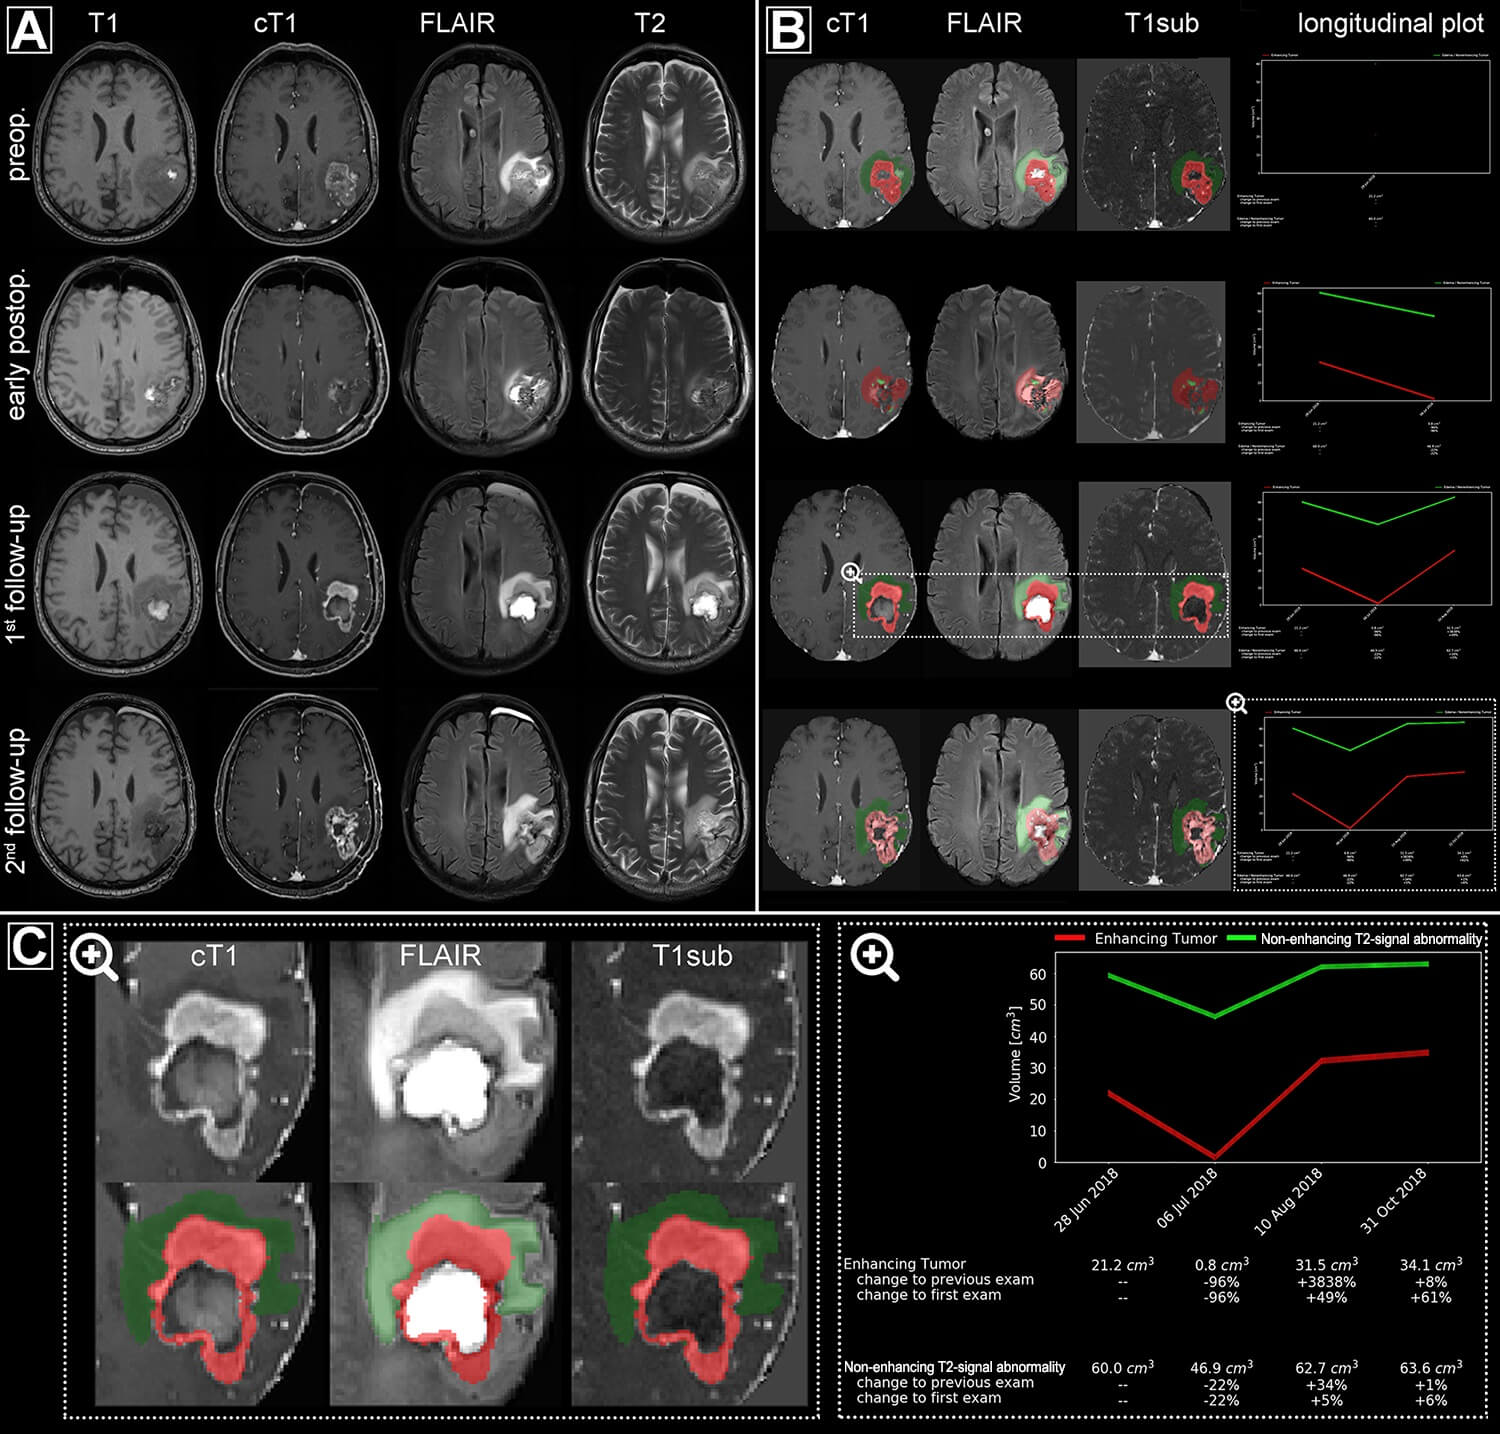

KI hilft, Therapieansprechen von Hirntumoren besser zu beurteilen . Welche Hirntumore nehmen Kontrastmittel auf? Glioblastome Glioblastome werden durch Hirndruckzeichen, Anfälle oder neurologische Ausfälle, wie z Die in den USA vorhergesagten angeblichen Hirnschäden habe ich nicht